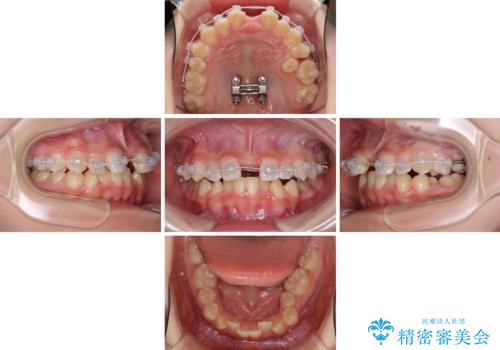

上下の骨幅を改善したことで、スムーズに歯列矯正を行うことができました。

インビザライン治療開始直後に遠方に引っ越しをされたため、通院間隔が長くなり、治療期間が長くなりましたが、しっかりと治療を行うことができました。